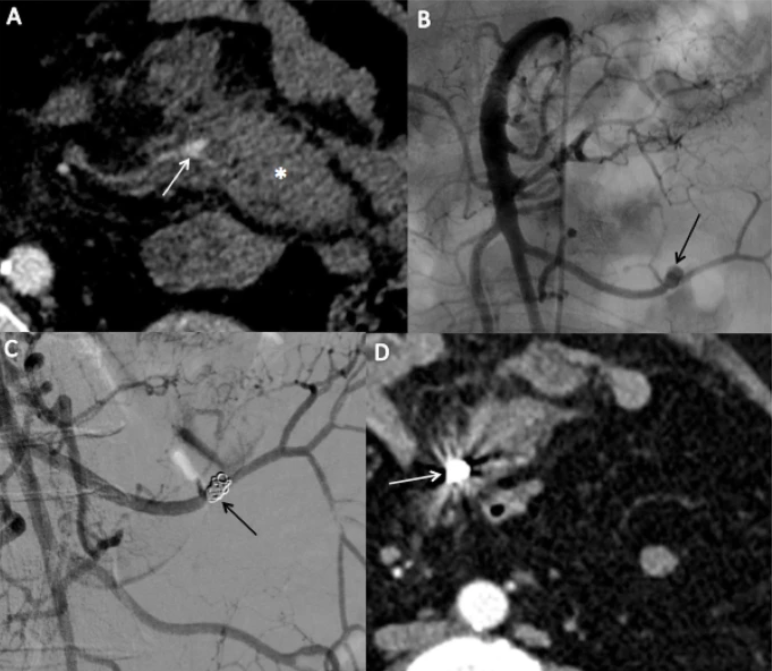

In this #originalarticle, the authors evaluated the safety and efficacy of #transarterialembolization for #mesenteric bleeding, building on the scarce literature for this alternative to emergency surgery Read + Download here: cvirendovasc.springeropen.com/articles/10.11…

In this #originalarticle, the authors evaluated the safety and efficacy of #transarterialembolization for #mesenteric bleeding, building on the scarce literature for this alternative to emergency surgery

Read + Download here:

cvirendovasc.springeropen.com/articles/10.11…